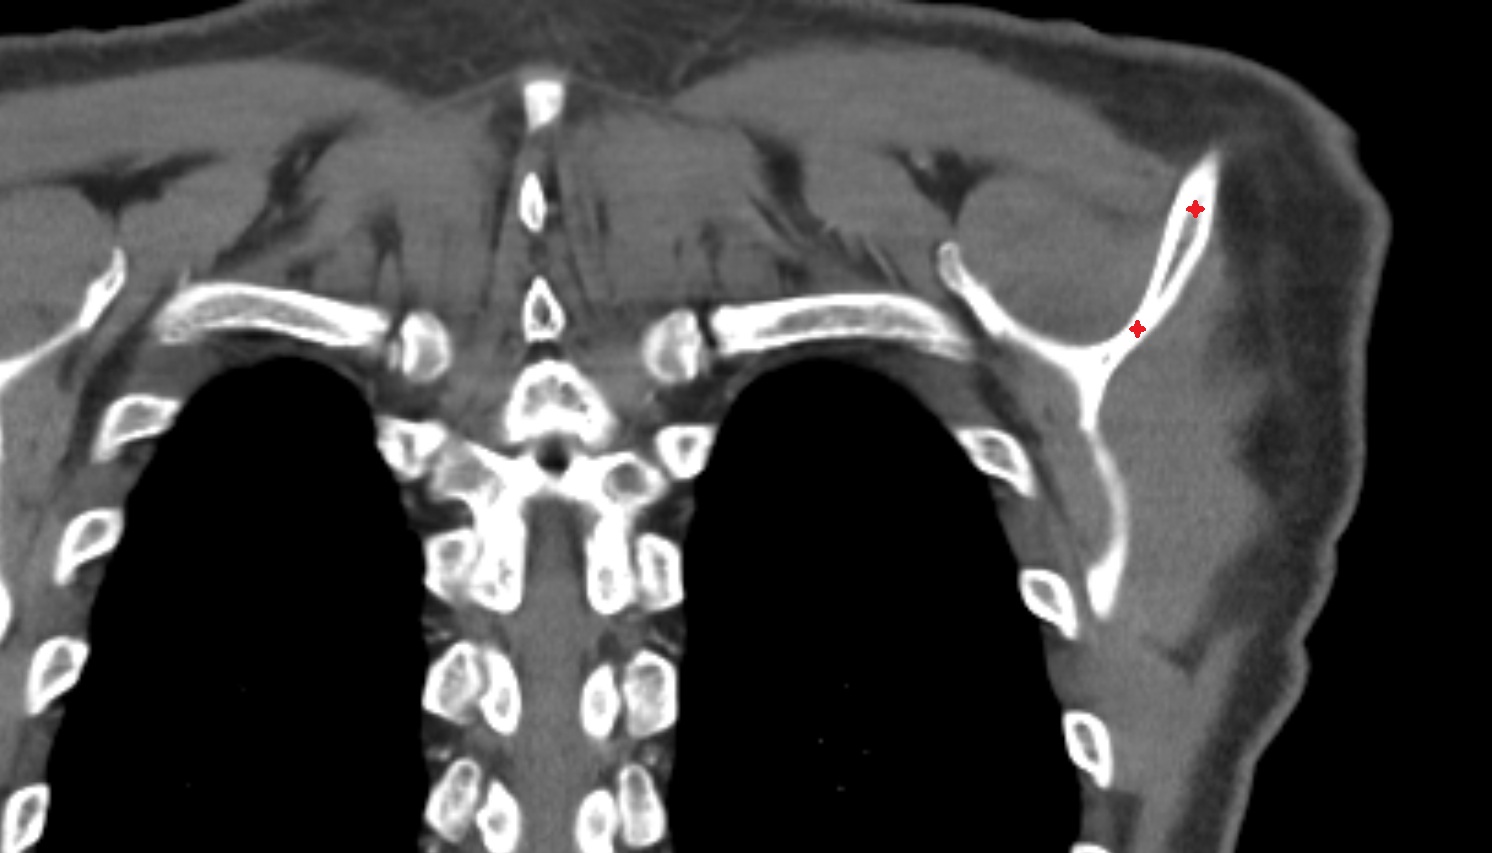

- Glenoid fossa

- Glenoid process of scapula

- Spine of scapula

- Acromion process of scapula

- Coracoid process of scapula

- Scapular body

- supraspinous fossa of scapula

- Subscapular fossa

- Neck of scapula

- Humerus

- Head of humerus